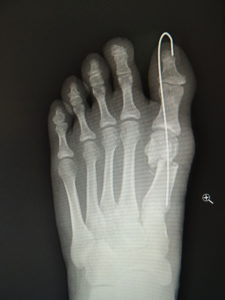

(図5)

手術前 手術後4年

(図6)

手術前 手術後

(図7)

真田理事長による手術の様子。外反母趾|症例 (左から 手術前、手術後、ワイヤ抜去後)